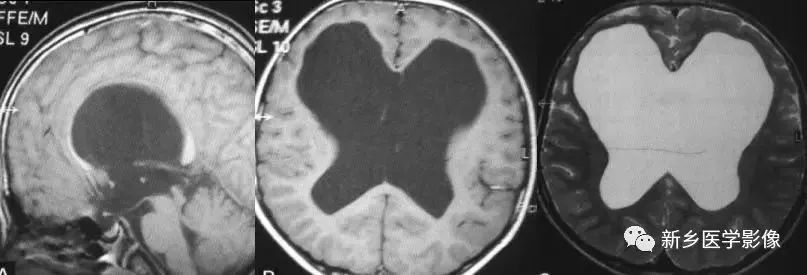

❹ Dandy-Walker’s综合症

又称第四脑室中侧孔先天性闭锁。在胚胎早期期,第四脑室正中孔及侧孔闭寒,导致四脑室呈囊性扩张,并伴有小脑蚓部及半球发育不良,扩张之四脑室向后发展,并与枕大池相连,使后颅窝扩大,小脑幕抬高。本病出现脑积水通常见于婴儿期,或者出生后即存在,但到成人期才发病。

前脑无裂畸形(holoprosencephaly):

是指一系列位于中线程度不同的畸形,累及大脑、面部、脑于和小脑。前脑未能够分开,呈不全性或完全性,端脑和间脑无法区分。根据脑及面部畸形程度将其分为无叶型、半叶型和单叶型。

- 无叶型前脑无裂畸形:最严重,端脑半球间没有裂隙,呈马蹄形或新月形扩大的单脑室跨越中线,与背侧囊交通。丘脑互相融合,面部畸形可有两眼距离过近、独眼畸形等。往往死于胎儿或新生儿期。

- 半叶型前脑无裂畸形:在前脑可见部分裂隙, 形成不同发育程度的大脑纵裂及大脑镰。两侧大脑半球在前部未完全分开,但枕叶和 双侧侧脑室体部分离,丘脑分开不完全。三脑室和海马发育不全,胼胝体仅可见到压部,而其他部分缺如额叶和基底节前部分辨不清。临床表现有两眼距离过近、唇裂、腭裂等面部畸形,侧脑室呈单一性且明显扩大。

- 单叶型前脑无裂畸形:与正常发育脑仅有些很小的区别,如透明隔缺如或双侧额叶不完全分开。